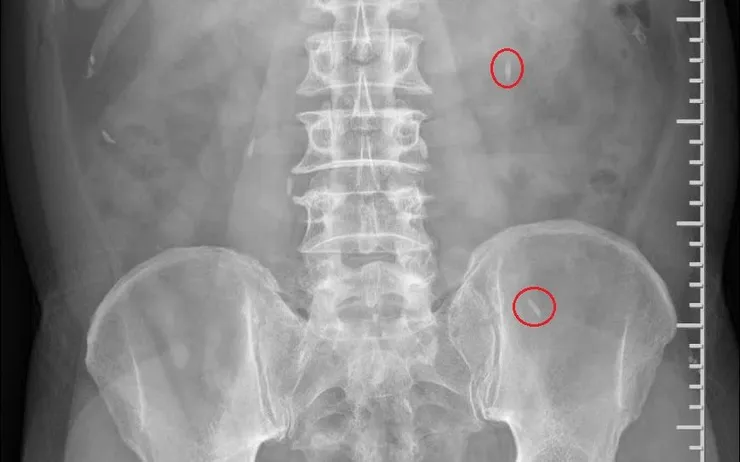

Bệnh nhân nam 74 tuổi đến khám trong tình trạng mệt mỏi, ăn uống kém, sút cân nhẹ. Qua thăm khám, bác sĩ phát hiện nhiều ký sinh trùng tồn tại trong cơ thể.

Khai thác tiền sử cho thấy người bệnh có thói quen ăn gỏi cá sống trong nhiều năm - yếu tố nguy cơ hàng đầu dẫn đến nhiễm ký sinh trùng đường tiêu hóa. Sau khi chẩn đoán, bệnh nhân được tư vấn và chỉ định điều trị phù hợp.